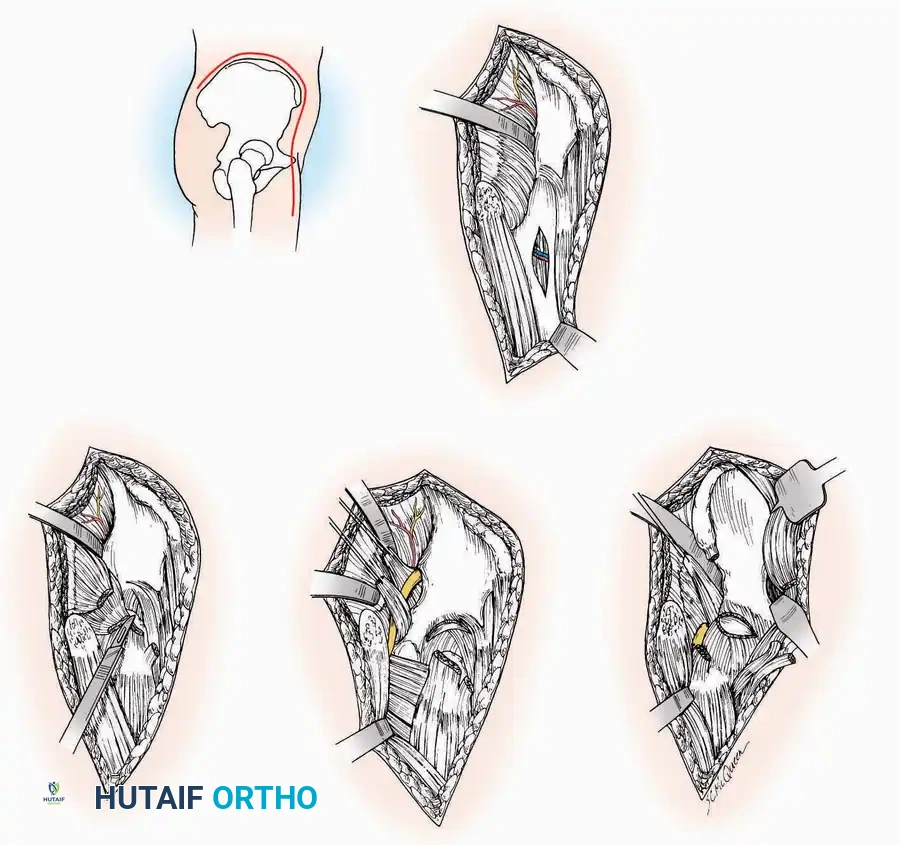

Lateral Approach (Extensile Lateral)

This is the workhorse approach for open reduction and internal fixation (ORIF) of displaced intra-articular calcaneal fractures.

Indications: ORIF of calcaneus fractures, lateral wall exostectomy, subtalar arthrodesis.

Positioning: Lateral decubitus with the operative leg up, or supine with a large bump under the ipsilateral hip to internally rotate the leg.

Surgical Technique:

* Incision: Begin the incision on the lateral margin of the Achilles tendon near its insertion. Extend it distally to a point 4 cm inferior and 2.5 cm anterior to the lateral malleolus. (For trauma, a classic L-shaped extensile incision is often used, dropping straight down anterior to the Achilles, then curving gently toward the base of the 5th metatarsal).

* Superficial Dissection: Divide the superficial and deep fasciae. It is imperative to create a "full-thickness" flap containing skin, subcutaneous fat, and periosteum to prevent flap necrosis.

* Nerve Protection: The sural nerve crosses the proximal and distal limbs of this approach. It must be identified and protected within the anterior flap.

* Deep Dissection: Isolate the peroneal tendons (longus and brevis). Incise and elevate the periosteum below the tendons to expose the lateral wall of the calcaneus.

* Tendon Management: If severe deformity or infection is present, the peroneal tendons may be divided via Z-plasty and repaired at the conclusion of the case, though this is rarely necessary in modern fracture care.